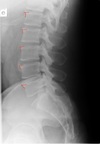

Lateral thoracic view

A

transverse process of c2-c7

LATERAL THORACIC LANDMARKS lateral thoracic view

disc spaces

108

endplate tips